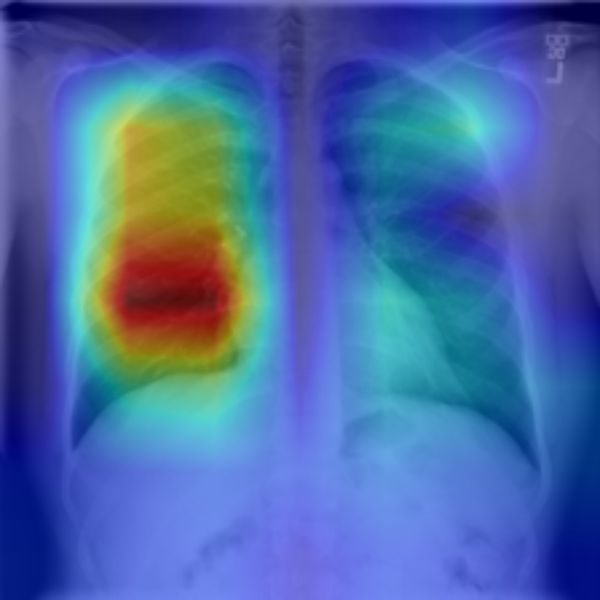

Grad-CAM [7] works by first propagating the input through the entire model. In a second step a desired class in the output is isolated by setting every other class to zero. The output of this isolated class is then backpropagated through the model up to the desired layer. Here the layer gradients are extracted and together with the feature maps of the same layer the attention map is computed. The result is a heatmap-like image of the attention at the desired layer as shown in figure 4. The approach of generating an attention map from a specific preferably high layer gives a good compromise between high-level semantics and detailed spatial information. Furthermore, by isolating a specific class Grad-CAM becomes class discriminant.

Refer to caption

Figure 4: The resulting Grad-CAM attention maps from the input images.